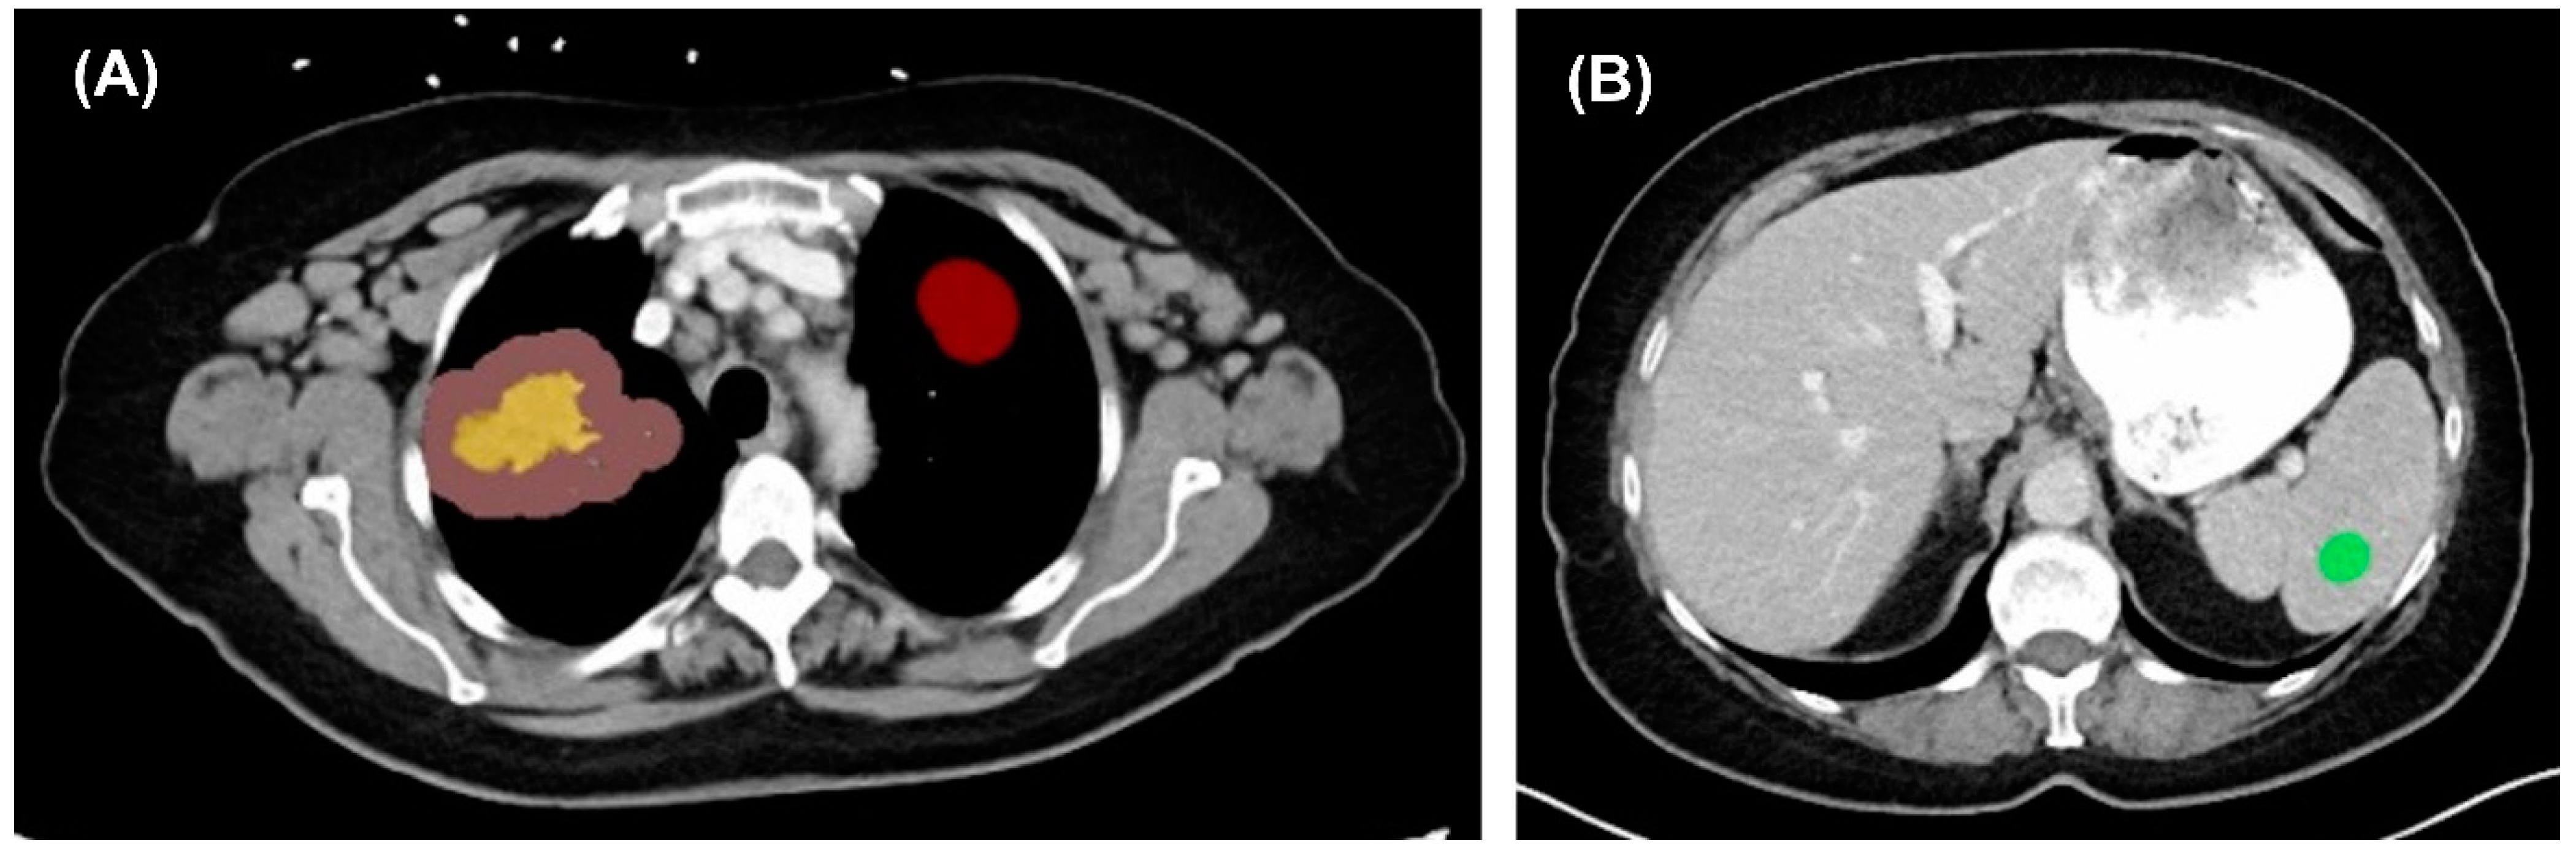

3.2. Image Segmentation and Feature Extraction